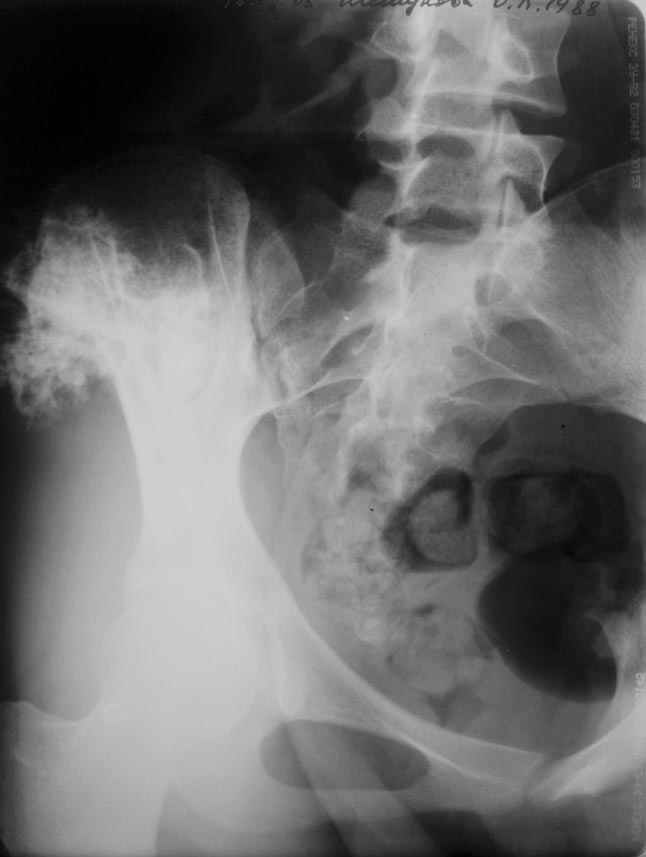

еще фото

В данный момент была выполнена биопсия новообразования. Материал в работе.

Получены результаты гистологического исследования.Процесс доброкачественный. Диагноз хондрома крыла таза подтвержден.Вопрос: чем и как закрыть предполагаемый значительный дефект крыла?